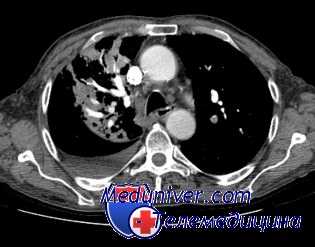

По совокупности клинических и лабораторных признаков у 42 больных установлен амилоидоз внутренних органов, от незначительных до выраженных, а у 33% — так называемые токсико-инфекционные изменения функции почек.

Амилоидные повреждения сочетались с другими угрожающими симптомами в течении заболевания (легочные кровотечения и кровохаркания, прогрессирование) и служили дополнительным указанием на необходимость оперативного вмешательства в связи с необратимостью основного патогенетического фактора, вызвавшего амилоидоз. Острая почечно-печеночная недостаточность в послеоперационном периоде развилась из 42 у 7 больных, из них у 4 с летальным исходом.

В отдаленный период прогресирование амилоидоза наблюдалось еще у 4 больных. У 31 больного послеоперационный период не сопровождался нарушениями функции паренхиматозных органов.